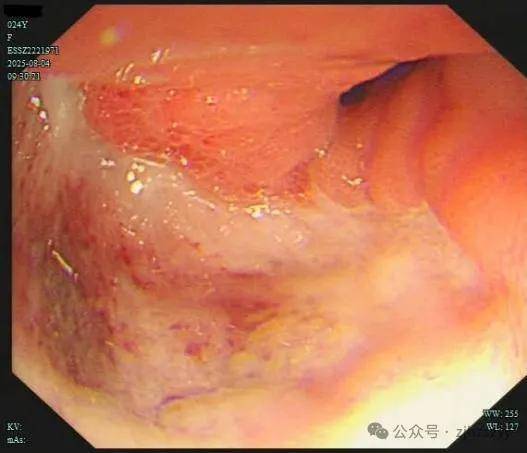

直到她开始频繁出现黑便,并在片场拍戏时几次呕血,才被同事紧急送往我院急诊。情况紧急,医生立即为小雯安排了急诊胃镜检查,发现她整个胃窦被一巨大的溃疡占据,黏膜组织变得僵硬、缺乏弹性,好似“皮革”一般。而随后的活检结果,更是给了这个年轻姑娘沉重一击——胃印戒细胞癌。

胃印戒细胞癌早期的隐匿性很强,在胃镜下表现也不明显,识别非常困难,可能表面看起来只是点、片状糜烂,而实际上已经多点生长。